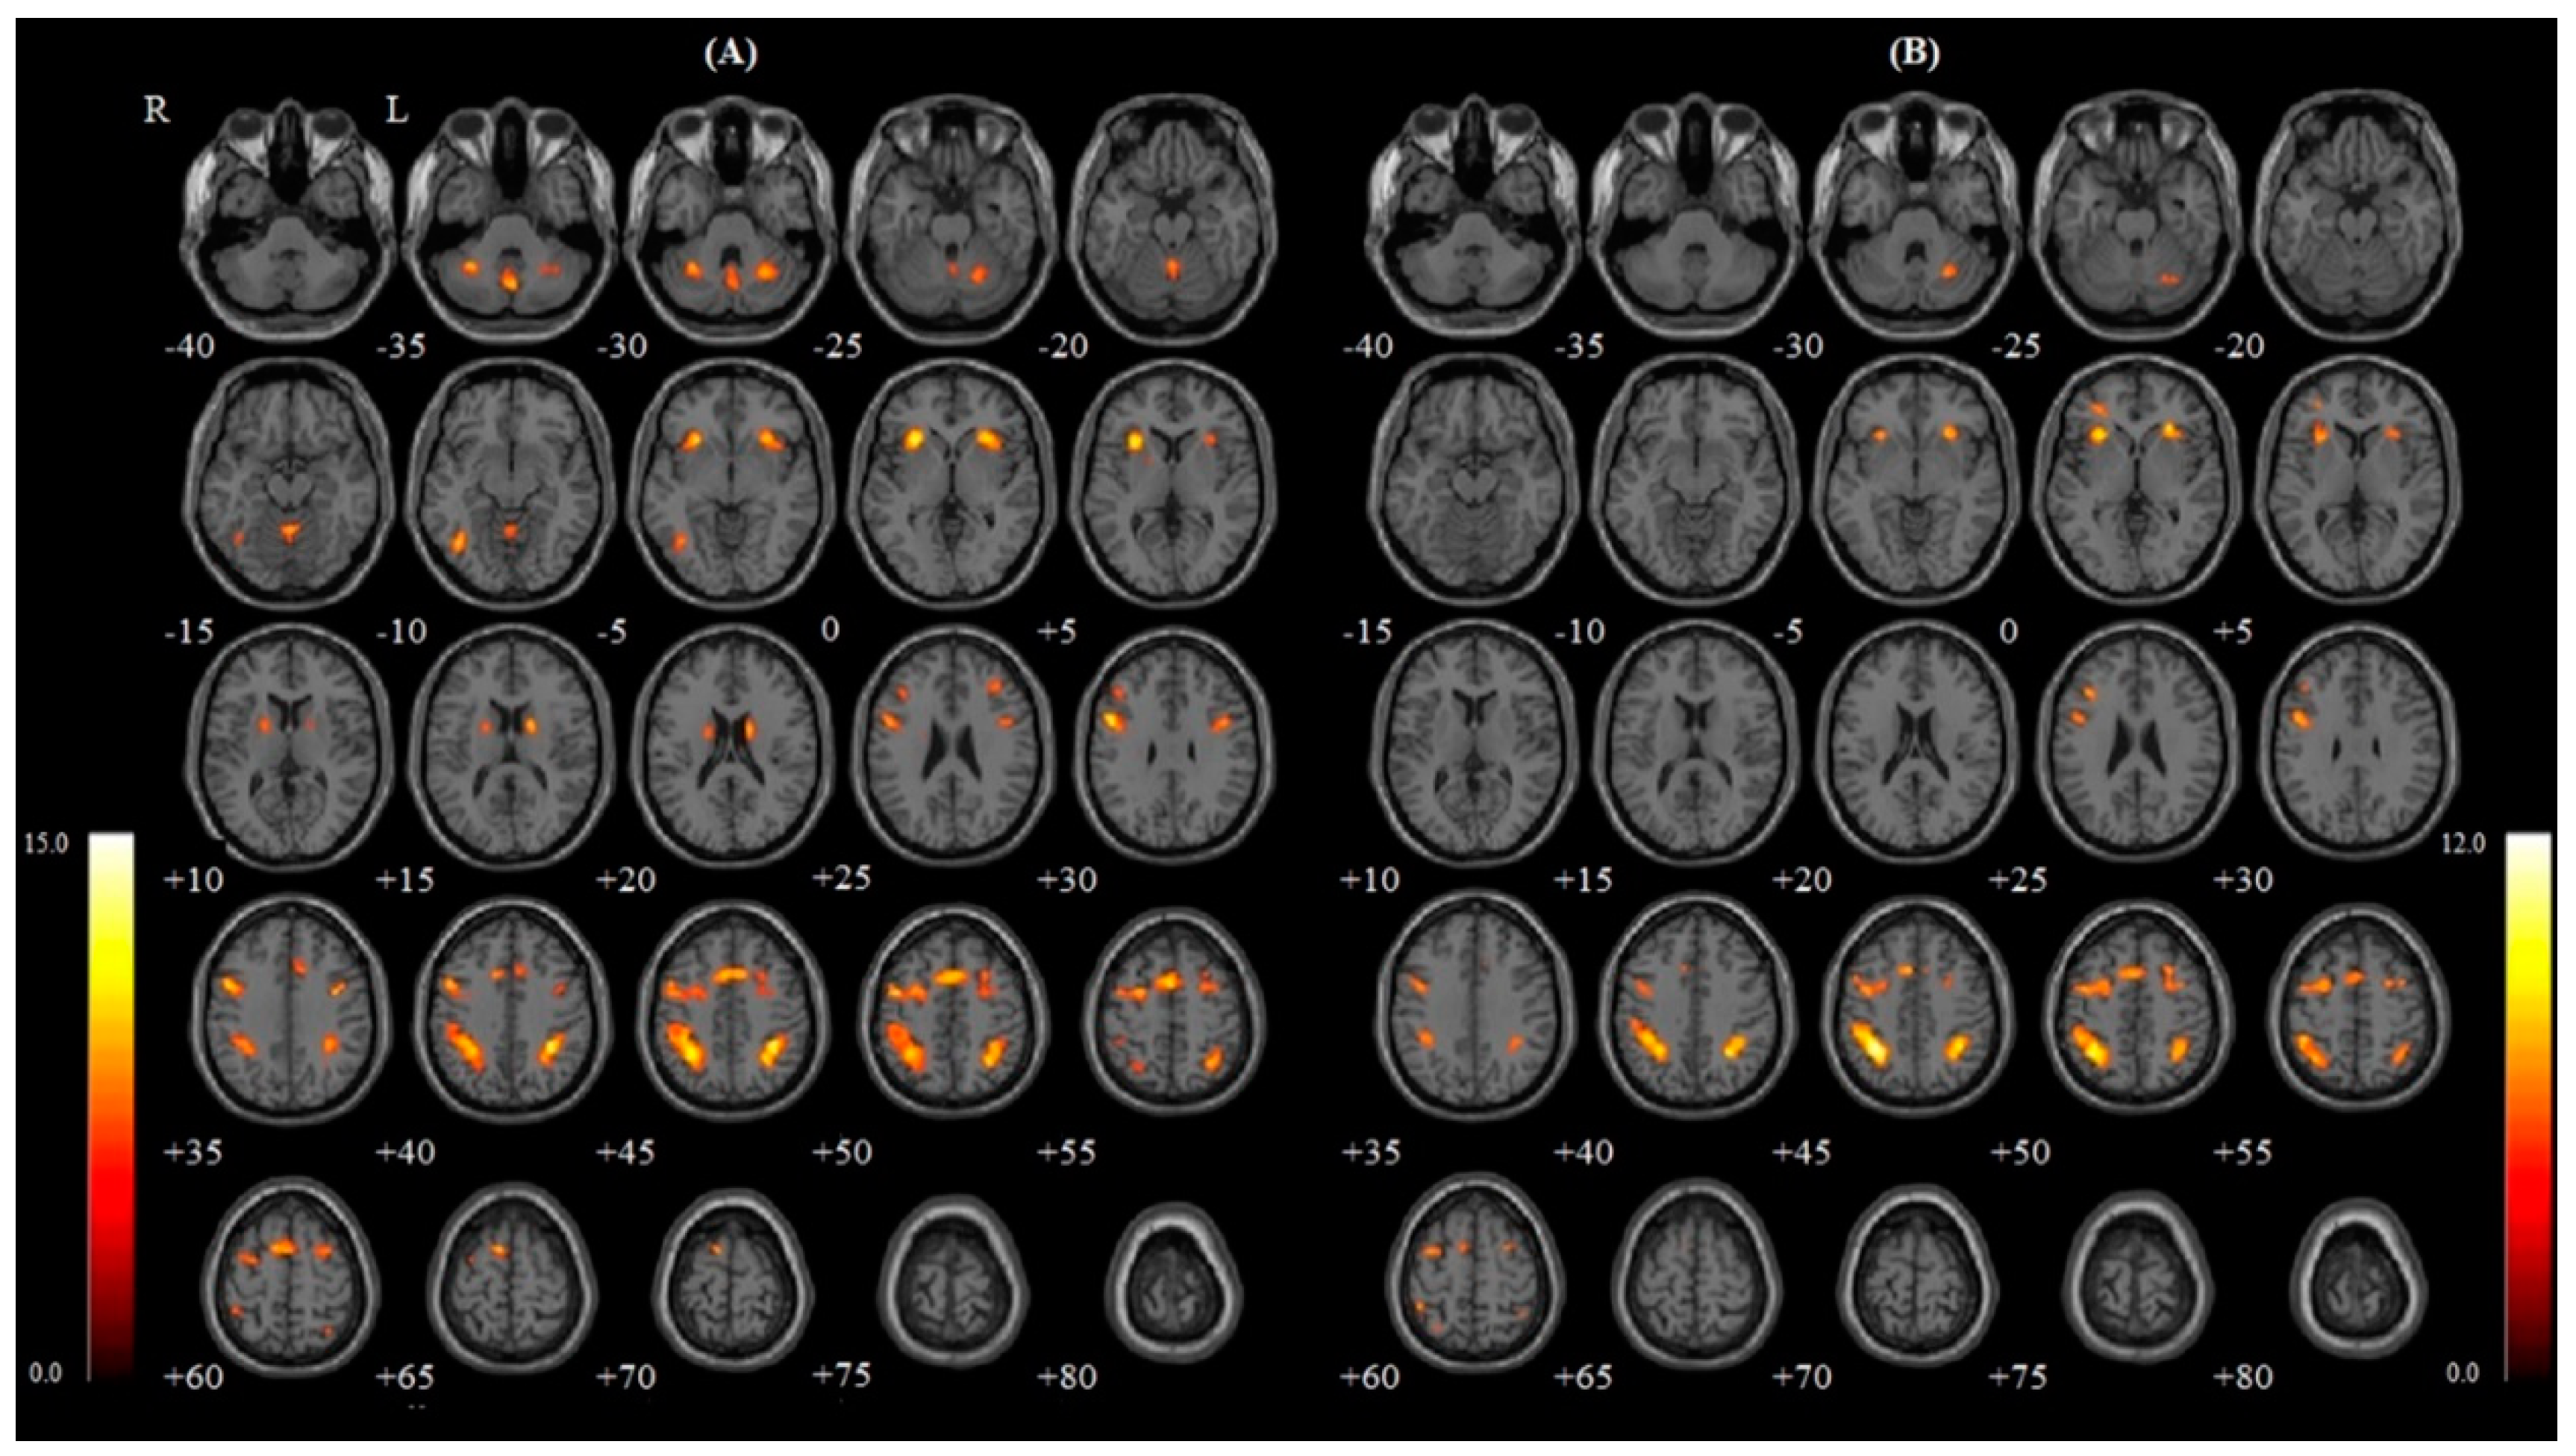

| Condition | L/R/M | Region | Cluster (KE) | Peak | Peak | Peak MNI Coordinate | ||

|---|---|---|---|---|---|---|---|---|

| T | Z score | X | Y | Z | ||||

| Nasal | R | Inferior parietal gyrus | 801 | 15.18 | 7.15 | 36 | −44 | 44 |

| Caudate nucleus | 133 | 11.33 | 7.15 | 16 | 2 | 18 | ||

| Insula | 291 | 11.26 | 6.34 | 30 | 22 | 0 | ||

| Cerebellum | 229 | 10.44 | 6.13 | 28 | −58 | −28 | ||

| Precentral gyrus | 184 | 10.17 | 6.05 | 38 | 0 | 34 | ||

| Middle frontal gyrus | 265 | 8.66 | 5.59 | 32 | 6 | 58 | ||

| M | Vermis | 413 | 9.89 | 5.97 | 0 | −66 | −34 | |

| L | Insula | 338 | 14.49 | 7.03 | −30 | 20 | 4 | |

| Precentral gyrus | 888 | 12.68 | 6.67 | −50 | 8 | 32 | ||

| Inferior parietal gyrus | 1295 | 12.68 | 6.67 | −30 | −48 | 44 | ||

| Inferior occipital gyrus | 177 | 11.42 | 6.38 | −40 | −62 | −8 | ||

| Supplementary motor area | 865 | 11.33 | 6.36 | 0 | 10 | 54 | ||

| Cerebellum | 127 | 10.39 | 6.11 | −30 | −54 | −30 | ||

| Middle frontal gyrus | 59 | 8.53 | 5.55 | −44 | 30 | 32 | ||

| Putamen | 153 | 8.24 | 5.45 | −20 | 4 | 12 | ||

| Oral | R | Inferior parietal gyrus | 568 | 11.48 | 6.39 | 36 | −46 | 46 |

| Putamen | 191 | 10.85 | 6.23 | 26 | 26 | 2 | ||

| Cerebellum | 102 | 8.81 | 5.64 | 26 | −62 | −28 | ||

| Superior frontal gyrus | 181 | 8.37 | 5.49 | 26 | 4 | 58 | ||

| L | Inferior parietal gyrus | 1201 | 13.89 | 6.92 | −32 | −48 | 46 | |

| Insula | 191 | 10.95 | 6.26 | −30 | 22 | 2 | ||

| Middle frontal gyrus | 73 | 10.61 | 6.17 | −30 | 44 | 2 | ||

| Supplementary motor area | 284 | 9.34 | 5.81 | 0 | 12 | 52 | ||

| Precentral gyrus | 655 | 9.15 | 5.75 | −46 | 4 | 30 | ||

| Inferior frontal gyrus, triangular part | 59 | 8.72 | 5.61 | −36 | 26 | 26 | ||